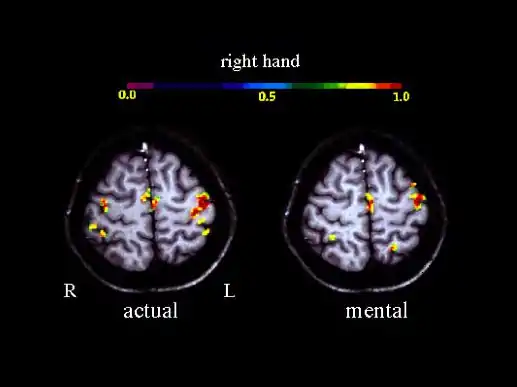

Велика кількість функціональних нейровізуалізаційних досліджень показали, що рухова уява пов'язана з активацією конкретних нейронних ланцюгів, що беруть участь в ранньому етапі контролю руху (програмування руху). Ці ланцюги включають в себе додаткову рухову зону, первинну моторну кору, нижню тім'яну кору, базальні ганглії і мозочок. [12][13] Такі фізіологічні дані є основою для розуміння загальних нейронних механізмів уяви і рухової підготовки.[14]